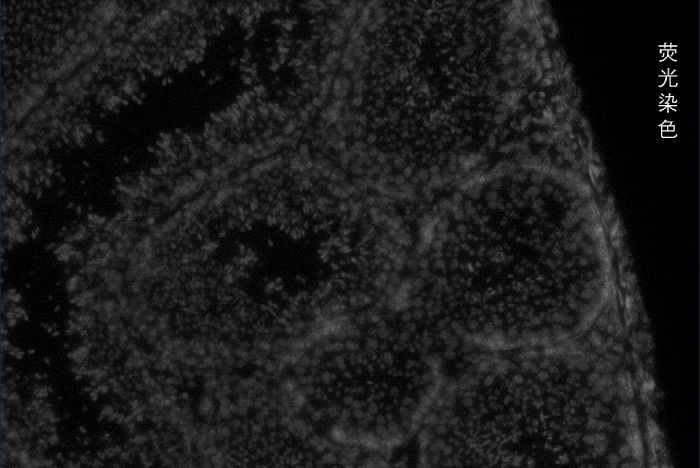

百創(chuàng)智造基于S系列空間芯片的底層設(shè)計,可以得到完全沒有錯誤的原片熒光圖像以及H&E圖像且與芯片完全對齊?;跓晒膺M(jìn)行細(xì)胞核的定位刻畫細(xì)胞核的邊界;基于HE的校準(zhǔn)輔助刻畫細(xì)胞的邊界,通過邊界信息映射到芯片上,提取相應(yīng)位置的測序數(shù)據(jù),實現(xiàn)精準(zhǔn)的單細(xì)胞分割。

2.原片熒光染色+原片H&E染色+原片空間測序相結(jié)合技術(shù):既可以進(jìn)行表達(dá)芯片H&E染色,又同時可以再表達(dá)芯片上進(jìn)行熒光染色,保證細(xì)胞分割更準(zhǔn)確。